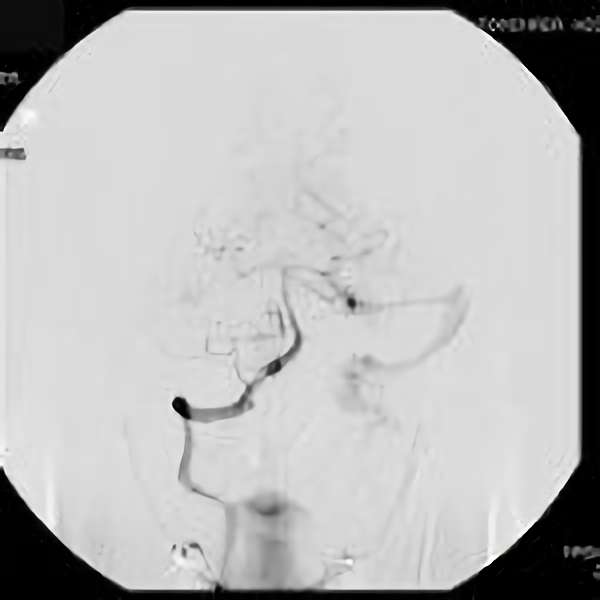

手術後

脳血管撮影により完全除去が確認された